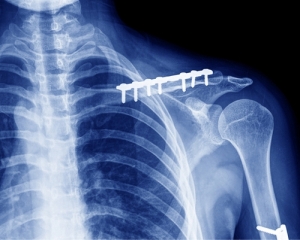

- Остеосинтез, выполняемый винтами, металлическими пластинами и болтами. Винты проводятся перпендикулярно оси кости, а пластины находятся на костной поверхности, такая ситуация похожа на дополнительную шину.

Способ синтеза, который выбирает врач, полностью зависит от характера и локализации перелома. При ключичных переломах чаще всего используется внутрикостная фиксация, которая выполняется с помощью металлического стержня. В этом случае не нужно накладывать гипсовую повязку. Нагрузка на руку допускается через месяц, а трудоспособность полностью восстанавливается через три месяца.

Врачи отмечают, что остеосинтез при переломе ключицы является эффективным методом лечения, позволяющим обеспечить стабильность и правильное сращение кости. Специалисты подчеркивают, что выбор техники остеосинтеза зависит от характера и локализации перелома. В случаях смещения фрагментов кости, особенно у активных пациентов, предпочтение отдается металлическим пластинам и винтам, которые обеспечивают надежную фиксацию.

В процессе операции могут использоваться и другие фиксаторы, например, пластинка Новикова, лавсановые ленты и гетероштифты. Спицы лучше не использовать, потому что они могут ломаться и изгибаться после операции.

Операция длится до двух часов. Проводится анестезия, после которой врач делает надрез. В отломках кости делают отверстия, в которые ставят края пластины. Затем кость прочно фиксируют в правильном положении, ушивают мягкие ткани.